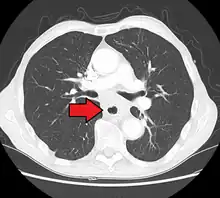

Esophageal cancer (lower part) as a result of Barrettʼs esophagus

Male predominance is particularly strong in this type of esophageal cancer, which occurs about 7 to 10 times more frequently in men.[25] This imbalance may be related to the characteristics and interactions of other known risk factors, including acid reflux and obesity.[25]